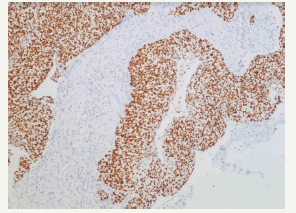

An upper endoscopy was performed and revealed the presence of a large amount of bilious content in the stomach and proximal duodenum. The third portion of the duodenum showed a proliferating violaceous mass, which was friable and completely obstructed the duodenal lumen (Figure 1). A CT scan evidenced a retroperitoneal mass infiltrating the duodenum, and was associated with dilatation of the proximal duodenum and stomach (Figure 2). An exploratory laparoscopy showed 8 x 8cm retroperitoneal mass involving the duodenum and para aortic lymph nodes. A palliative gastro jejunostomy bypass was performed. The pathologic study of the biopsies showed epithelial cells with corneal pearls and the immunehystochemistry study was positive for p63, confirming the diagnosis of squamous cell carcinoma of the cervix (Figure 3 & 4). Our patient improved with the above mentioned palliative bypass surgery

Figure 4:Positivity of the immunohistochemistry with the marker p63.